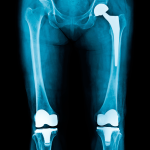

Knie und Hüfte im Fokus